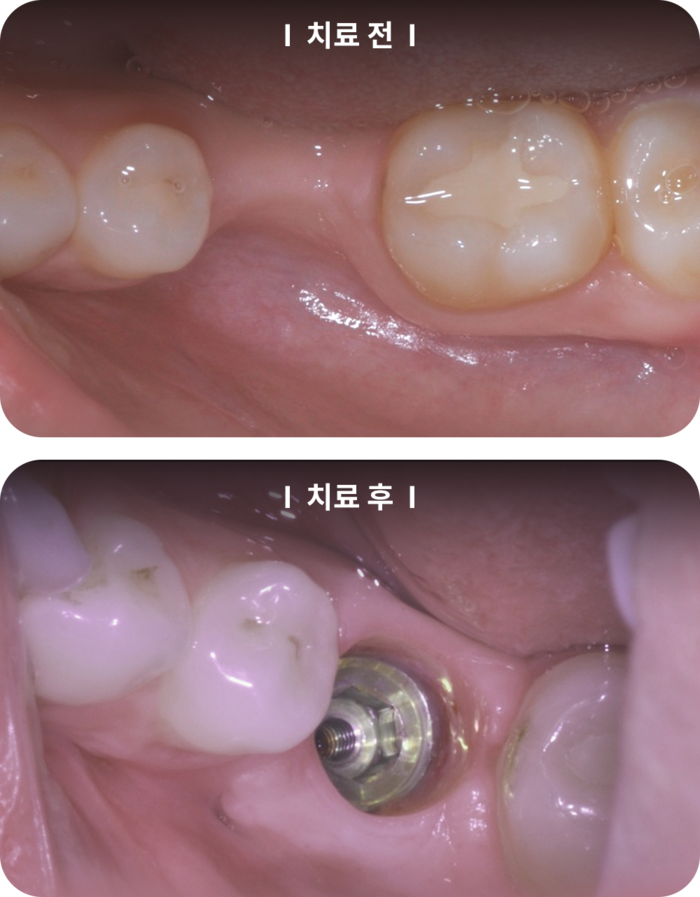

치료 전후 사례

치료 전후의 사례를 살펴보면, 잇몸 치료의 중요성을 더욱 실감할 수 있습니다. 예를 들어,

에서는 치료 전 잇몸이 많이 내려앉은 상태의 사진과 치료 후 건강한 잇몸 상태의 사진을 비교할 수 있습니다. 치료 후에는 치아의 외관이 개선되고 잇몸 건강이 회복된 것을 확인할 수 있습니다.